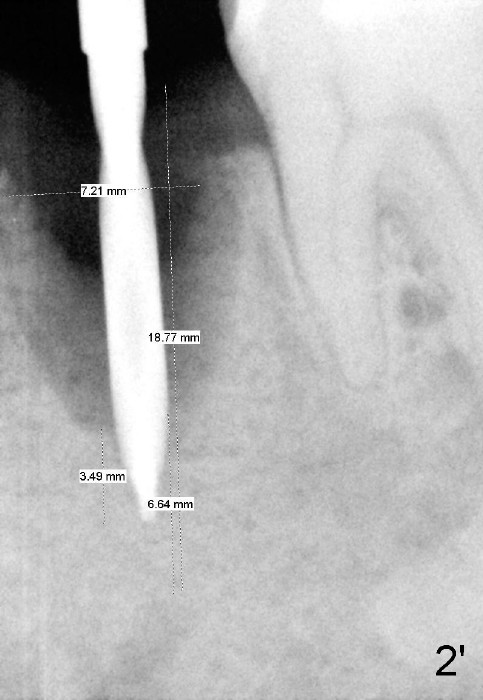

To avoid injury to the mental loop (Fig.2 dashed line), the depth of initial osteotomy is tightly controlled apical to the bottom of the socket. Accurate measuring is the 2nd important measure to assure no or minimal neurological trauma. The wide socket (due to infection) allows to place an implant as wide as 7 mm.

Each of intraop PAs (Fig.2-5) is accompanied by one without labeling the mental loop. For example, Fig.2'. This shows the importance to delineate it every time X-ray taken. Sometimes it is not easy to identify the boundary of the nerve.